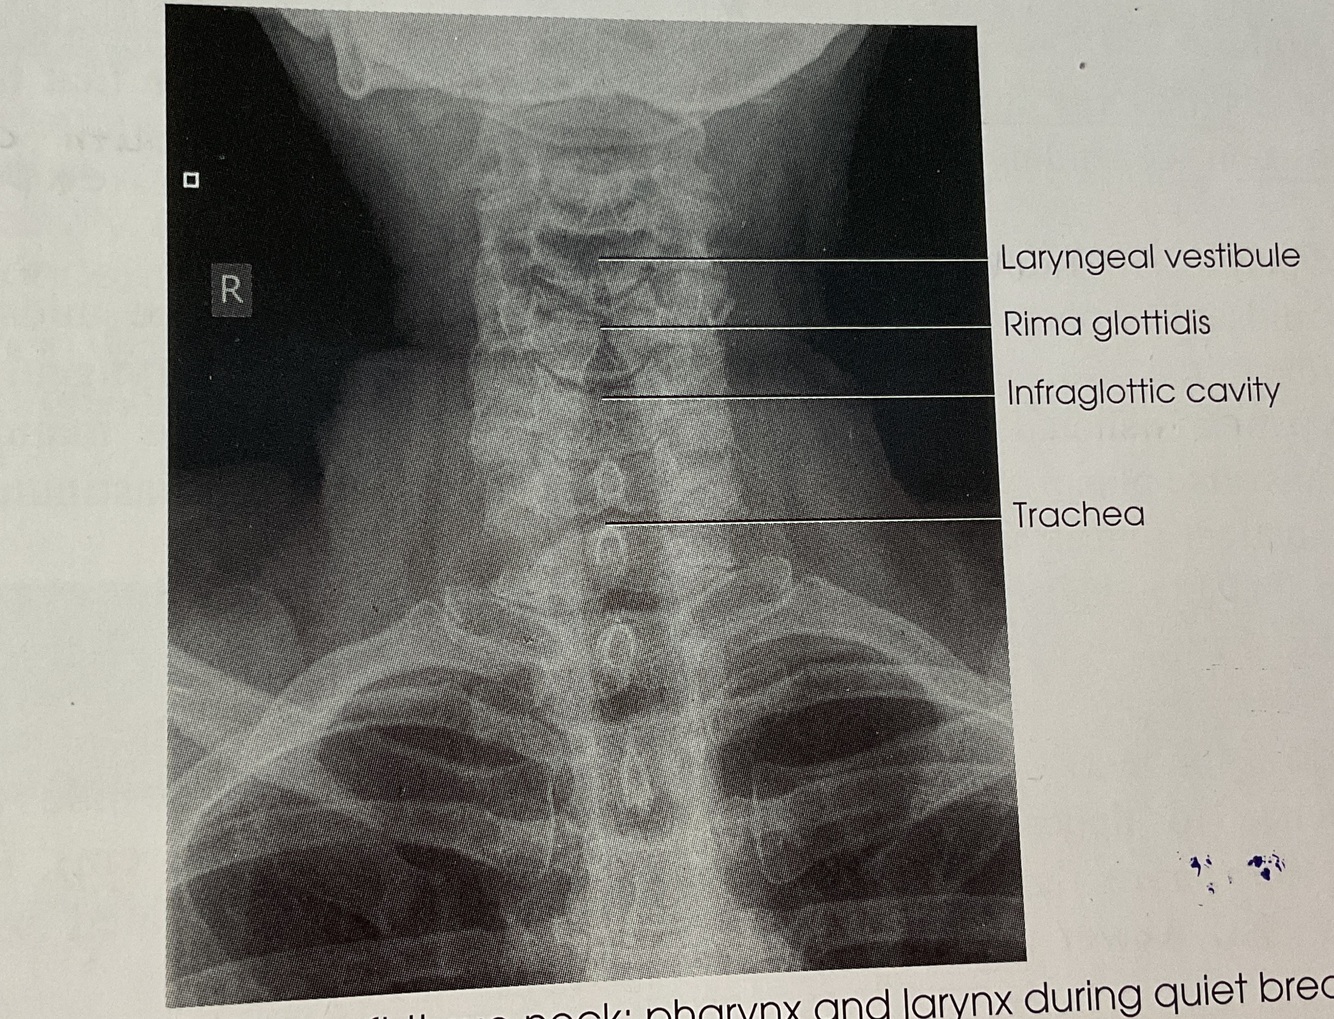

~ Air-Filled Upper Airway (From pharynx to prox trachea)

~ No rotation or tilt of Cervical Spine

SUPERIMPOSED Zygapophyseal joints & OPEN Intervertebral joints

~ Air Filled Upper Airway from Pharynx to Proximal. trachea (UPPER AIRWAY)

~ AIr filled airway from midcervical to midthoracic region (TRACHEA & SUPERIOR MEDIASTINUM)